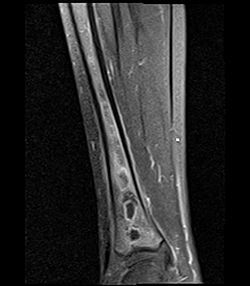

Como ocorre a classificação de osteomielite?

Contiguidade (80%): adultos (pé diabético)

Hematogênica (20%): crianças (metáfise ossos longos), adultos (diáfise ossos longos, vertebras)

Agente etiológico principal da osteomielite e o relacionado a anemia falciforme? Como tratar?

Mais comum: s. aureus … oxacilina ou cefazolina ou vancomicina

Anemia falciforme: salmonella… ceftriaxone

Tempo: 4-6 semanas … vertebral 6-8 semanas

Como realizar o diagnóstico de osteomielite?